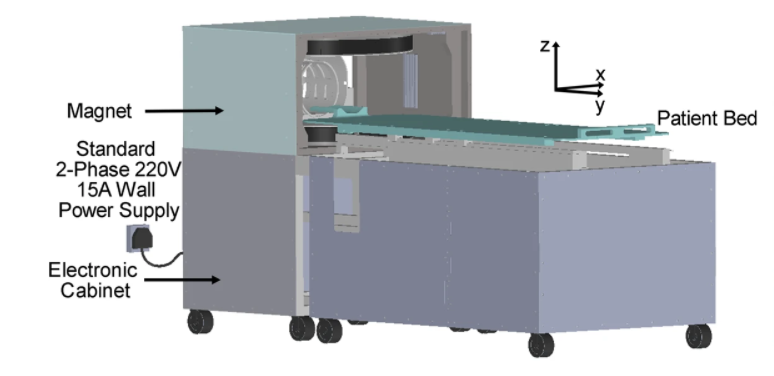

Researchers from the University of Hong Kong (HKU) have successfully developed a new magnetic resonance imaging (MRI) technology, the ultralow field (ULF) 0.055 Tesla brain MRI, which can operate from a standard AC wall power outlet and requires neither radiofrequency nor magnetic shielding room.

With the use of a deep learning algorithm, Professor Wu’s team has removed the constraint in conventional MRI, namely the need to be shielded from outside radiofrequency signal, which results in a bulky, non-mobile set-up. The existing MRI scanners are essentially a giant magnet, and need a purpose-built room to shield them from outside signals and to contain the powerful magnetic fields generated by their superconducting magnets, which require costly liquid helium cooling systems.

A conventional, typical MRI machine can cost up to US$3 million, yet the ULF-MRI scanner costs only a fraction of this price.